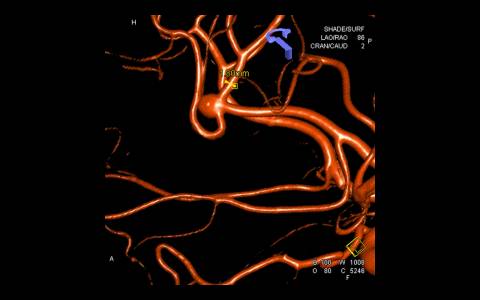

Realizado angiografia cerebral e reconstrução 3D sendo evidenciado um aneurisma de colo largo com ramo frontal emergindo do colo do aneurisma. Baseado nessas característica, foi optado por tratamento com stent redirecionado de fluxo Fred Jr., associado a micromolas de platina devido o importante inflow do ramo frontal.

Implantado um stent 2,5 x 18mm conforme programação 3D. O procedimento transcorreu sem intercorrência, mantendo a patência dos vasos envolvidos.